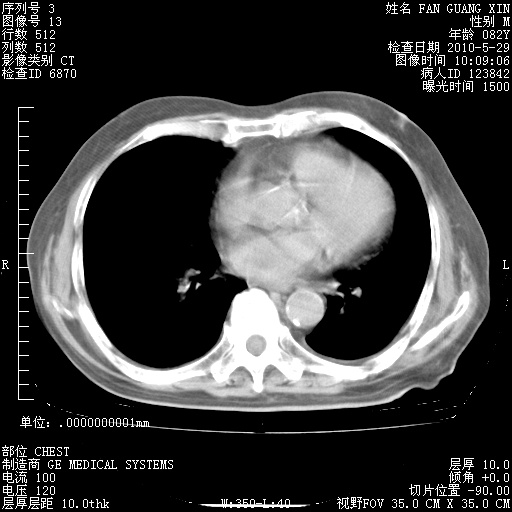

再治疗10天后的肺部CT 纵膈窗

阅读此次胸部CT,肺间质渗出性改变较入院时有吸收。目前从体温、白细胞、中性分叶明显增高,肯定存在细菌感染(发生医院感染哦,若无消化道及泌尿系统等感染的依据,肺部感染可能大)。若你院头孢哌酮舒巴坦钠耐药率较高,同意你的方案,若48小时体温仍高,可考虑使用碳青霉稀类抗菌药物,同时可予超声雾化、注意滴数时加大液体量。白蛋白33.30g/L较低哦,需加强营养等支持治疗。